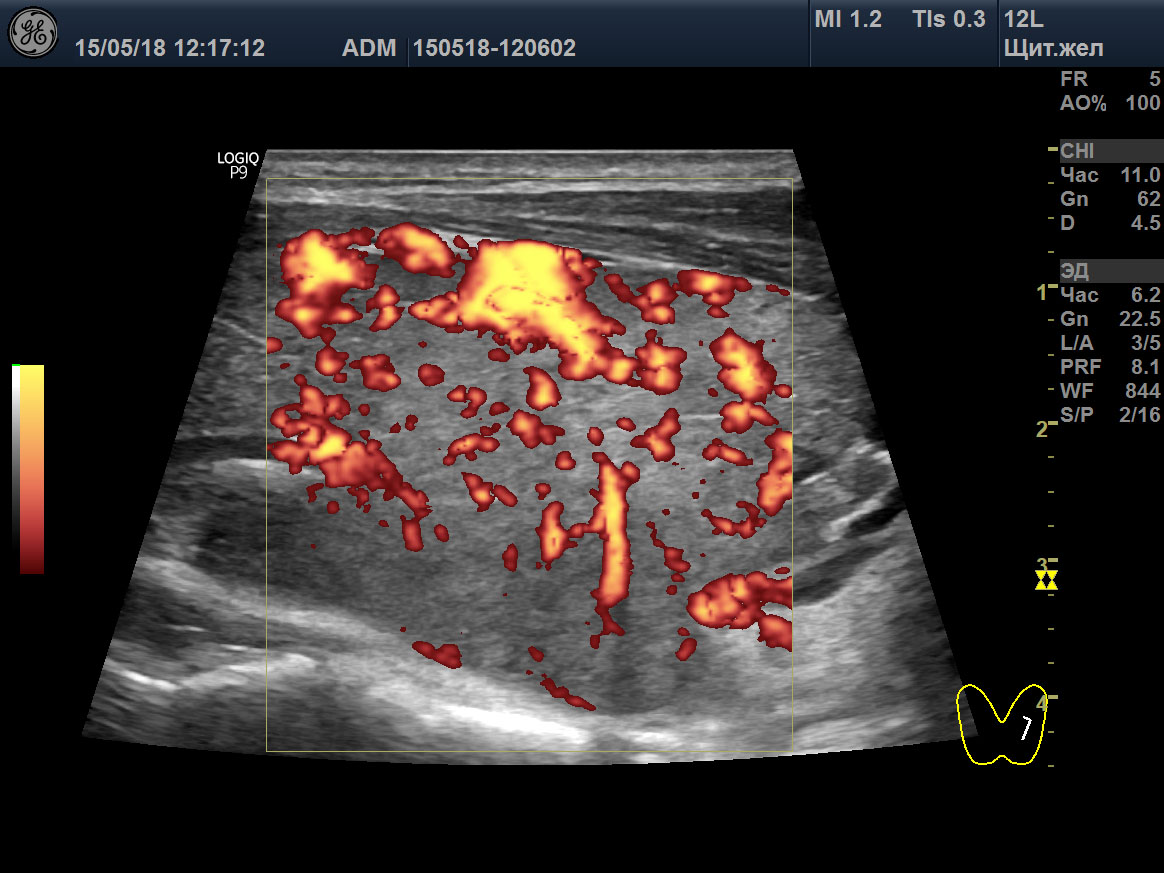

15 мая 2018 ультразвуковое исследование (УЗИ) щитовидной железы выявило зоб 3 степени (объём 45 мл; 23,6D + 21,4S), признаки умеренного отёка стромы (гомогенная гипоэхогенность паренхимы), значительное усиление интенсивности кровотока, систолическую пиковую скорость (SPV) кровотока в системе верхних щитовидных артериях (STA) 123 cm/sec справа и 160 cm/sec слева (рисунок: A, B, C).

A

B

C

D

E

F

Изображения щитовидной железы пациента в режиме Допплера. A, B, C ― до лечения (15 мая 2018), и D, E, F после лечения (23 августа 2021). A, D ― поперечная проекция левой доли. B, E ― продольная проекция левой доли. C, F ― SPV STA слева.

Одновременно с восстановительной динамикой гормонального и иммунного обмена в отношении щитовидной железы, УЗИ также показывало значительное улучшение (таблица 2). Через 10 месяцев (13 февраля 2019) было выявлено изменение объёма железы до 30,4 мл, уменьшение отёка стромы и снижение интенсивности кровотока. SPV STA стали 38 cm/sec справа и 47 cm/sec слева.